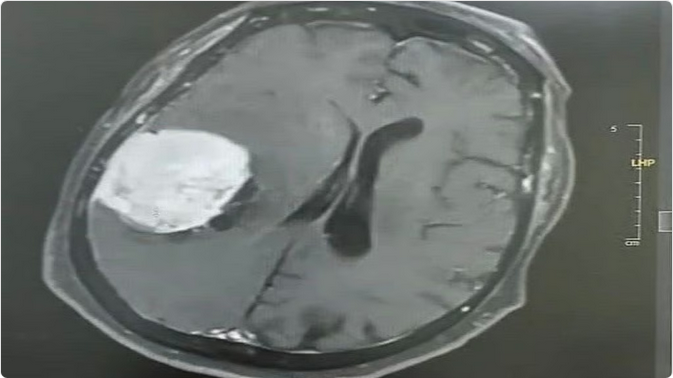

تمكّن فريق طبي متخصص بمستشفى ينبع العام عضو تجمع المدينة المنورة الصحي من إجراء عملية نوعية دقيقة لاستئصال ورم دماغي كبير بحجم (٥×٥×٤ سم) لسيدة تبلغ من العمر 80 عامًا، كانت تعاني من صداع مزمن وضعف متزايد في الجانب الأيسر من الجسم حتى أصبحت غير قادرة على الحركة وطريحة الفراش.

وأوضح تجمع المدينة المنورة الصحي أن المستفيدة راجعت المستشفى وهي تعاني من الأعراض المذكورة، وبعد إجراء الفحوصات السريرية وصور الرنين المغناطيسي تبيّن وجود ورم كبير في الجهة الجدارية اليمنى من الدماغ، وبعد التنسيق مع الأقسام ذات العلاقة واستكمال التحضيرات الطبية، أُدخلت المريضة إلى غرفة العمليات حيث نجح الفريق الطبي – بفضل الله – في استئصال الورم بالكامل بدقة عالية دون مضاعفات.